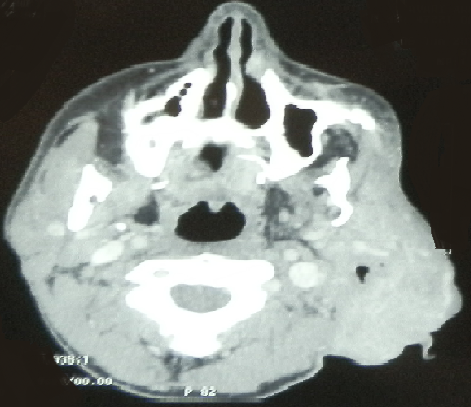

La neurofibromatose de type 1 (NF1), appelée également maladie de Von Recklinghausen, est une affection autosomique dominante caractérisée par son polymorphisme clinique. Les neurofibromes dans le La neurofibromatose de type 1 (NF1), appelée également maladie de Von Recklinghausen, est une affection autosomique dominante caractérisée par son polymorphisme clinique. Les neurofibromes dans le cadre de cette maladie peuvent être cutanés, sous-cutanés ou plexiformes. Les neurofibromes plexiformes siègent surtout au niveau des paupières, du tronc et des membres. La localisation dans la région cervico-faciale est rare. L'examen clinique et l'imagerie, sont souvent suffisants pour poser le diagnostic. L'évolution est imprévisible justifiant une surveillance clinique et radiologique prolongée. Patient âgé de 21 ans, suivi pour une neurofibromatose de Von Recklinghausen, a consulté pour une tuméfaction de l'hémiface gauche de 5 cm de grand axe. L'examen a révélé une hypoplasie de la mandibule, des os frontal et temporal gauches, une oreille gauche bas implantée. A la palpation, il avait deux tuméfactions pigmentées de consistance molle: la première étendue depuis la loge parotidienne vers la loge submandibulaire, et la deuxième siégeant au niveau de la conque et comblant le méat auditif externe. A la tomodensitométrie cervico-faciale, il avait un volumineux processus expansif de 11x10x5 cm centré sur la loge parotidienne gauche, avec une parotide complètement envahie par ce processus. Cette masse infiltre le méat auditif externe en dehors et les muscles ptérygoïdiens et la graisse parapharyngée en dedans. Cet aspect était évocateur d'un neurofibrome plexiforme. Il a bénéficié d'une plastie du pavillon gauche. L'évolution était marquée par la stabilisation de la taille de la tumeur faciale.cadre de cette maladie peuvent être cutanés, sous-cutanés ou plexiformes. Les neurofibromes plexiformes siègent surtout au niveau des paupières, du tronc et des membres. La localisation dans la région cervico-faciale est rare. L’examen clinique et l’imagerie, sont souvent suffisants pour poser le diagnostic. L’évolution est imprévisible justifiant une surveillance clinique et radiologique prolongée.